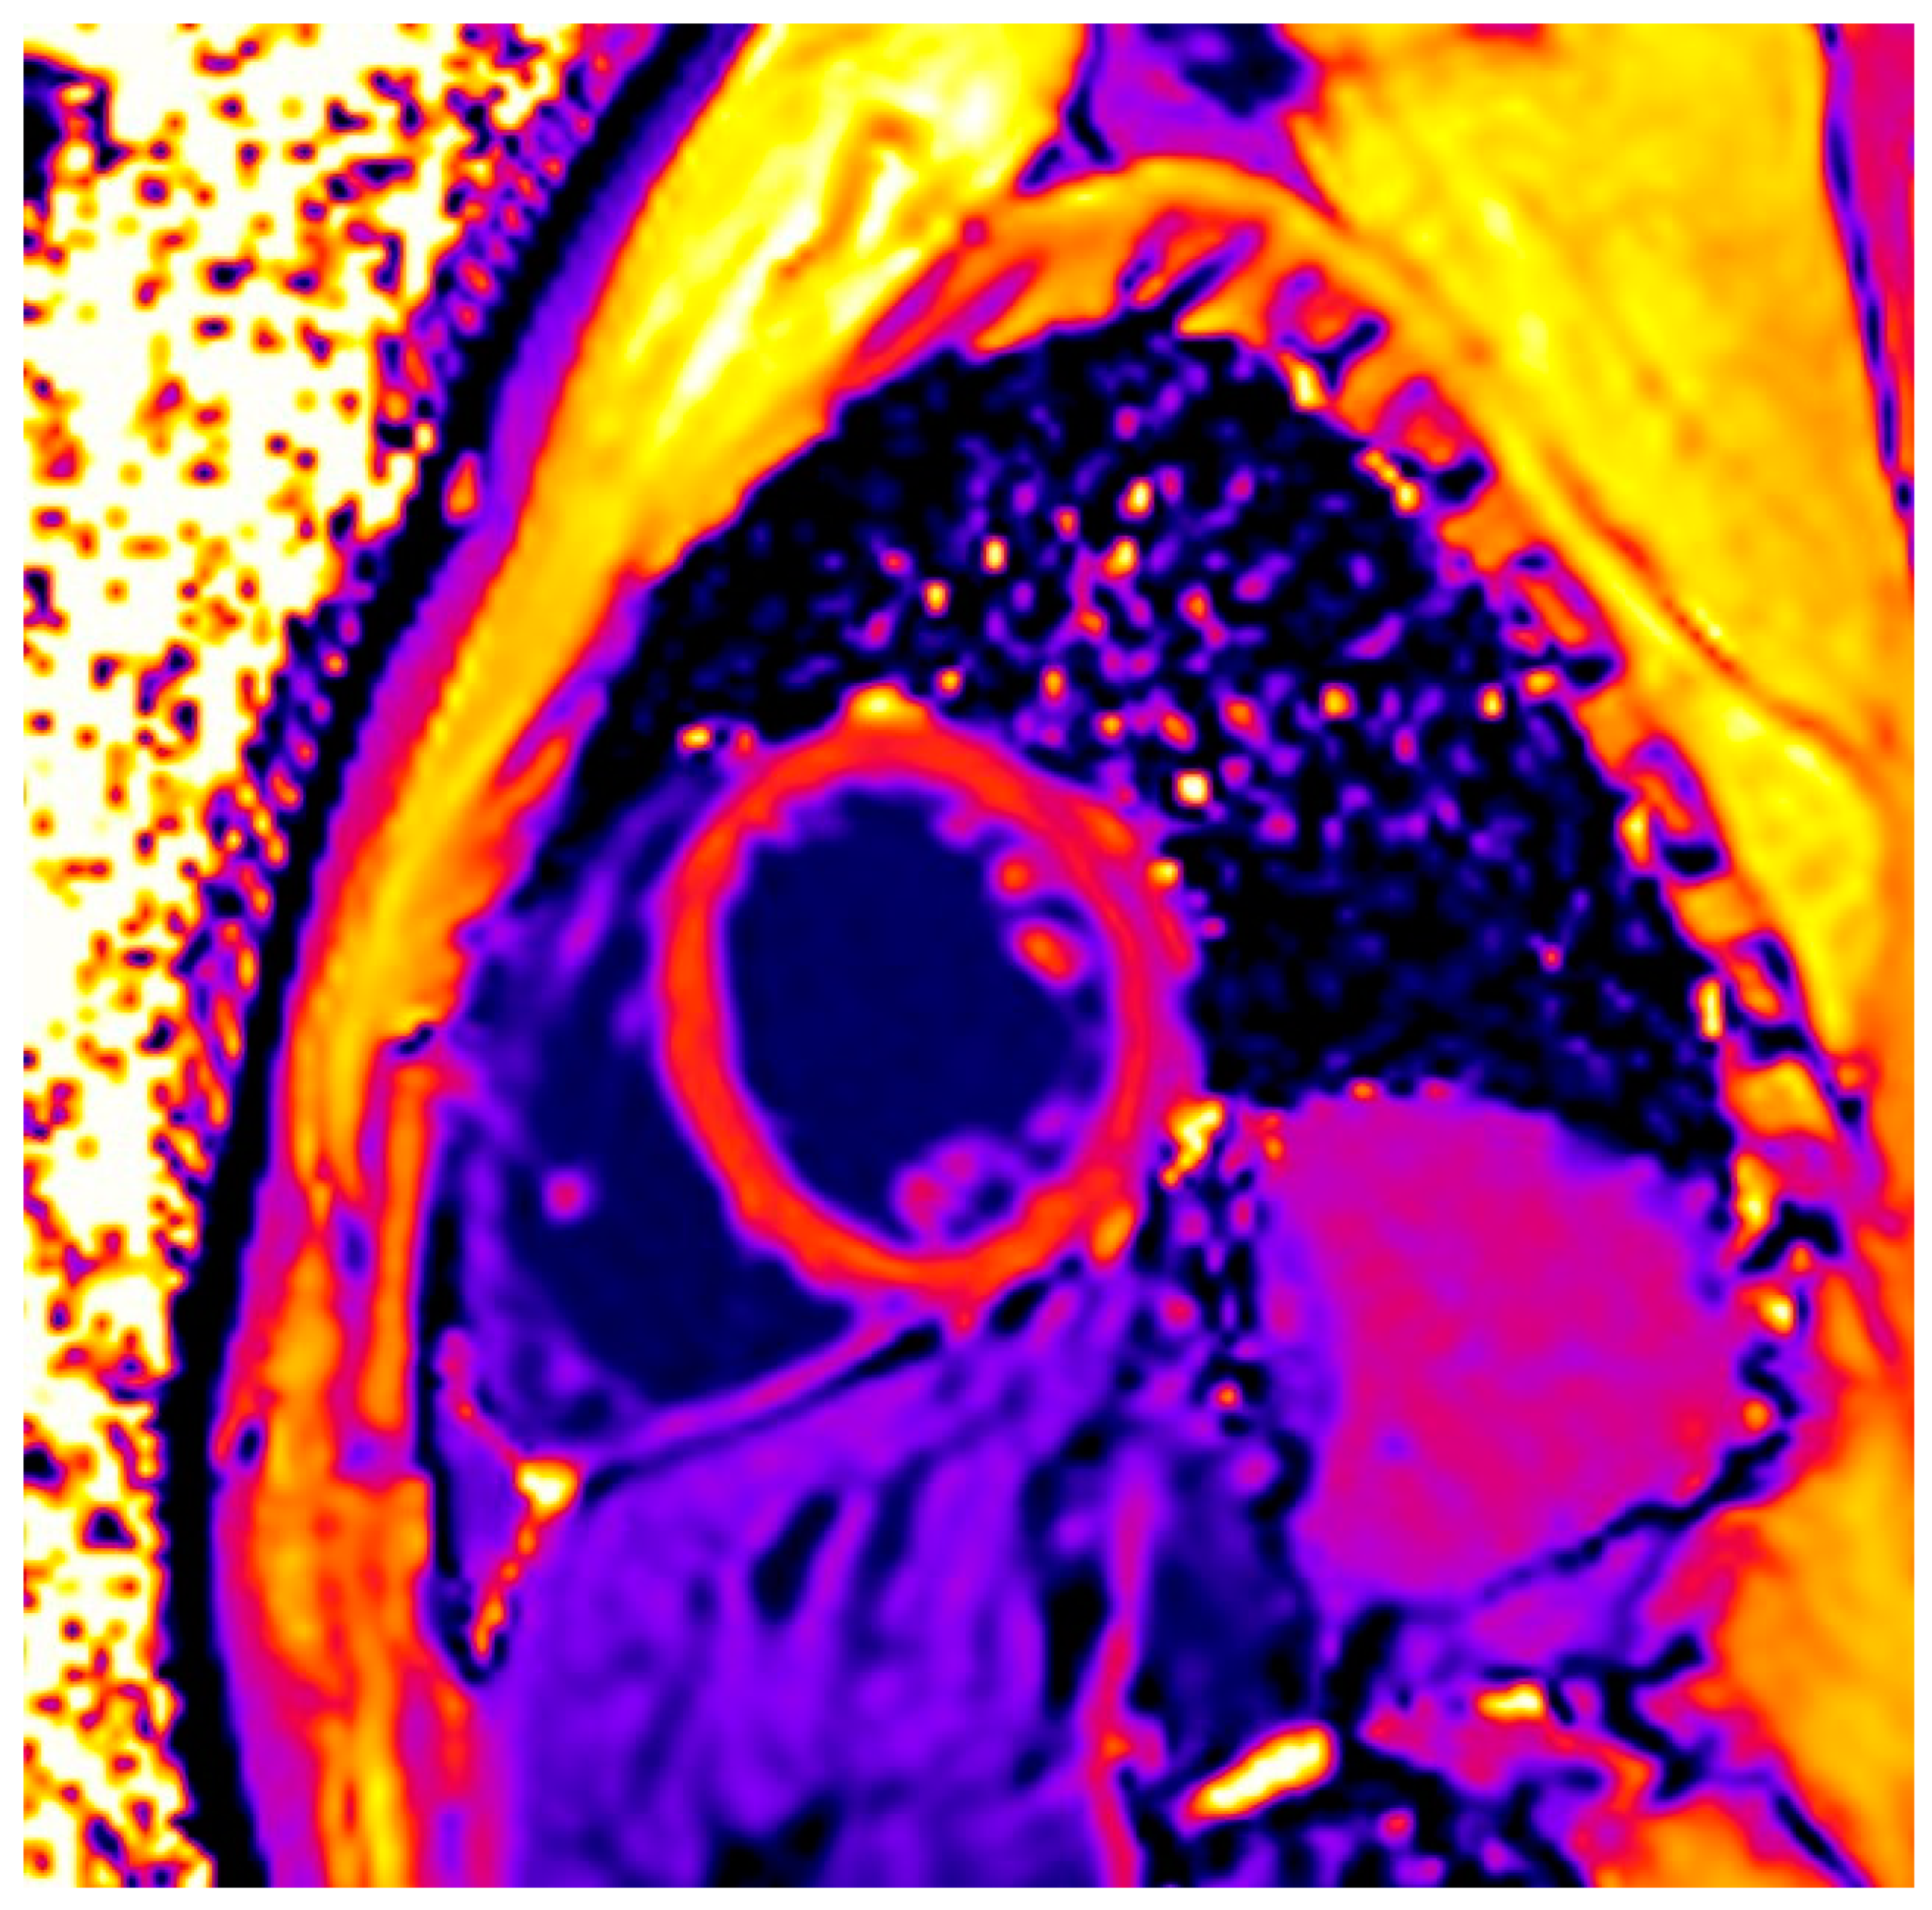

| Non-ischemic LGE | 149 (86%) |

| ≥1 pathologic T1 index | 141/145 (97%) |

| ≥1 pathologic T2 index | 62/173 (36%) |

| Both positive T1- and T2-criterion | 48/145 (33%) |